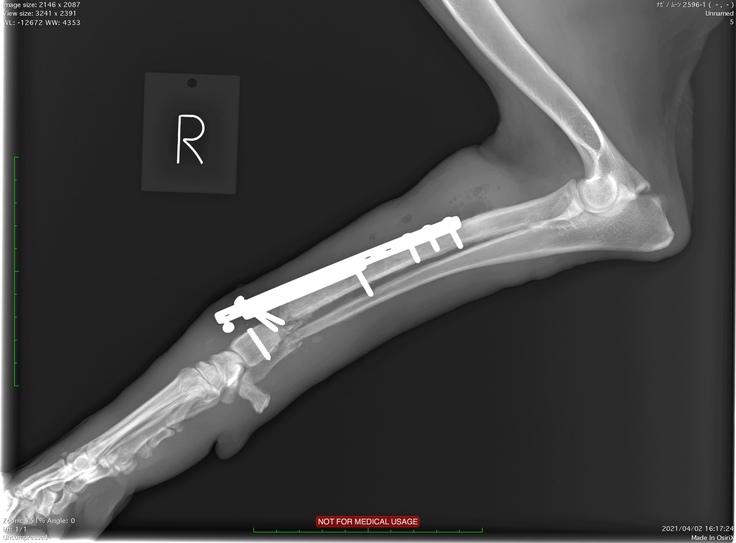

大津動物クリニックではクラウドファンディングのお話をしたらレントゲンの画像もご提供いただけました。

2度目の手術前のレントゲンです。

足先側のビス(釘)が折れて足が曲がってしまっています。

2度目の手術後のレントゲンです。まっすぐになりました。